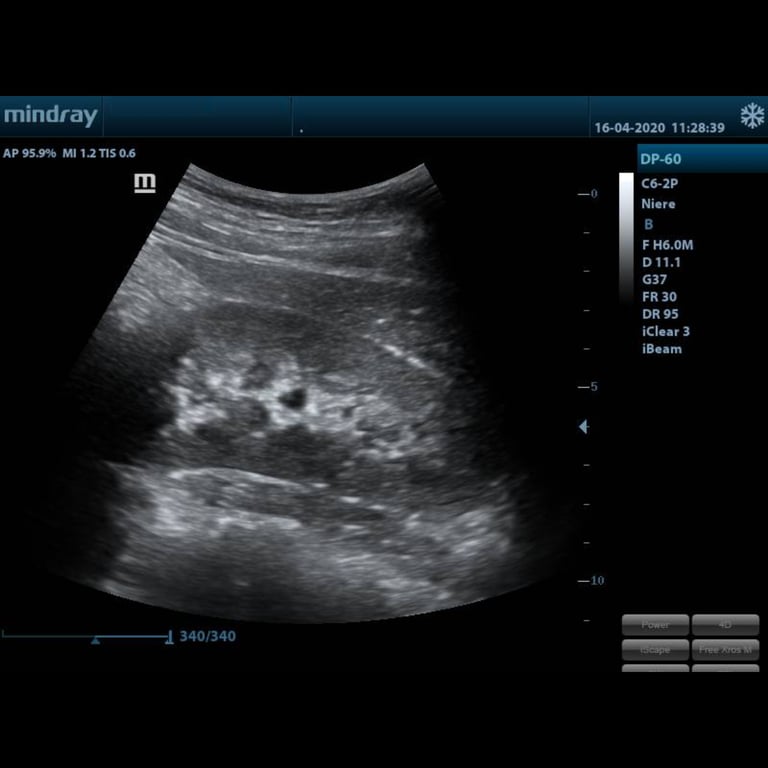

Galerie · DP-60

Das DP-60 im Bild

DP-60 Display Ultraschallbild